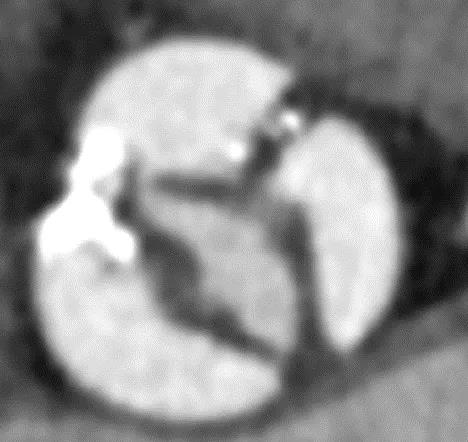

患者男性,67岁,头晕伴胸闷、胸痛6月余,术前心脏超声提示主动脉瓣增厚钙化伴重度狭窄,峰值流速4.9m/s,峰值压差94mmHg,平均跨瓣压差59mmHg,瓣口面积0.6cm2。CT显示主动脉瓣为Type I型二叶瓣,瓣叶边缘及左右冠瓣融合嵴严重钙化,致瓣口极度细窄。瓣环面积528.8mm2,测算直径25.9mm,左冠脉开口高度14.4mm,右冠脉开口高度17.5mm。患者合并重度肺气肿、多发肺大泡、支气管扩张,肺功能极差,静息状态下氧饱和度仅约80%,STS评分8.6%,属于外科手术高风险患者。

CT重建显示患者双侧髂动脉、股动脉、锁骨下动脉质量极差,多发钙化狭窄伴局部夹层,无法经股动脉和锁骨下动脉入路。而且患者重度肺气肿致心脏两侧受压,心尖被压缩在胸骨及肋弓骨性融合后方,亦无法经心尖入路。评估双侧颈动脉近端均有钙化斑块伴轻度狭窄,平均管径约6mm,左侧管径略大于右侧。颅内Willis环交通支通畅,可以耐受经单侧颈动脉介入手术。